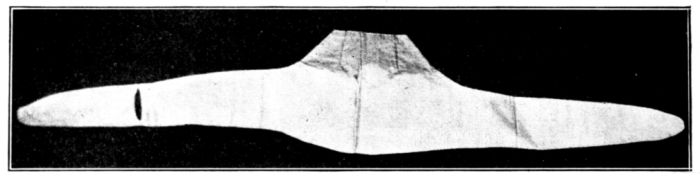

| 37. | Abdominal binder used in above | 124 |

| 43. | Delivery pad of newspapers and old muslin | 161 |